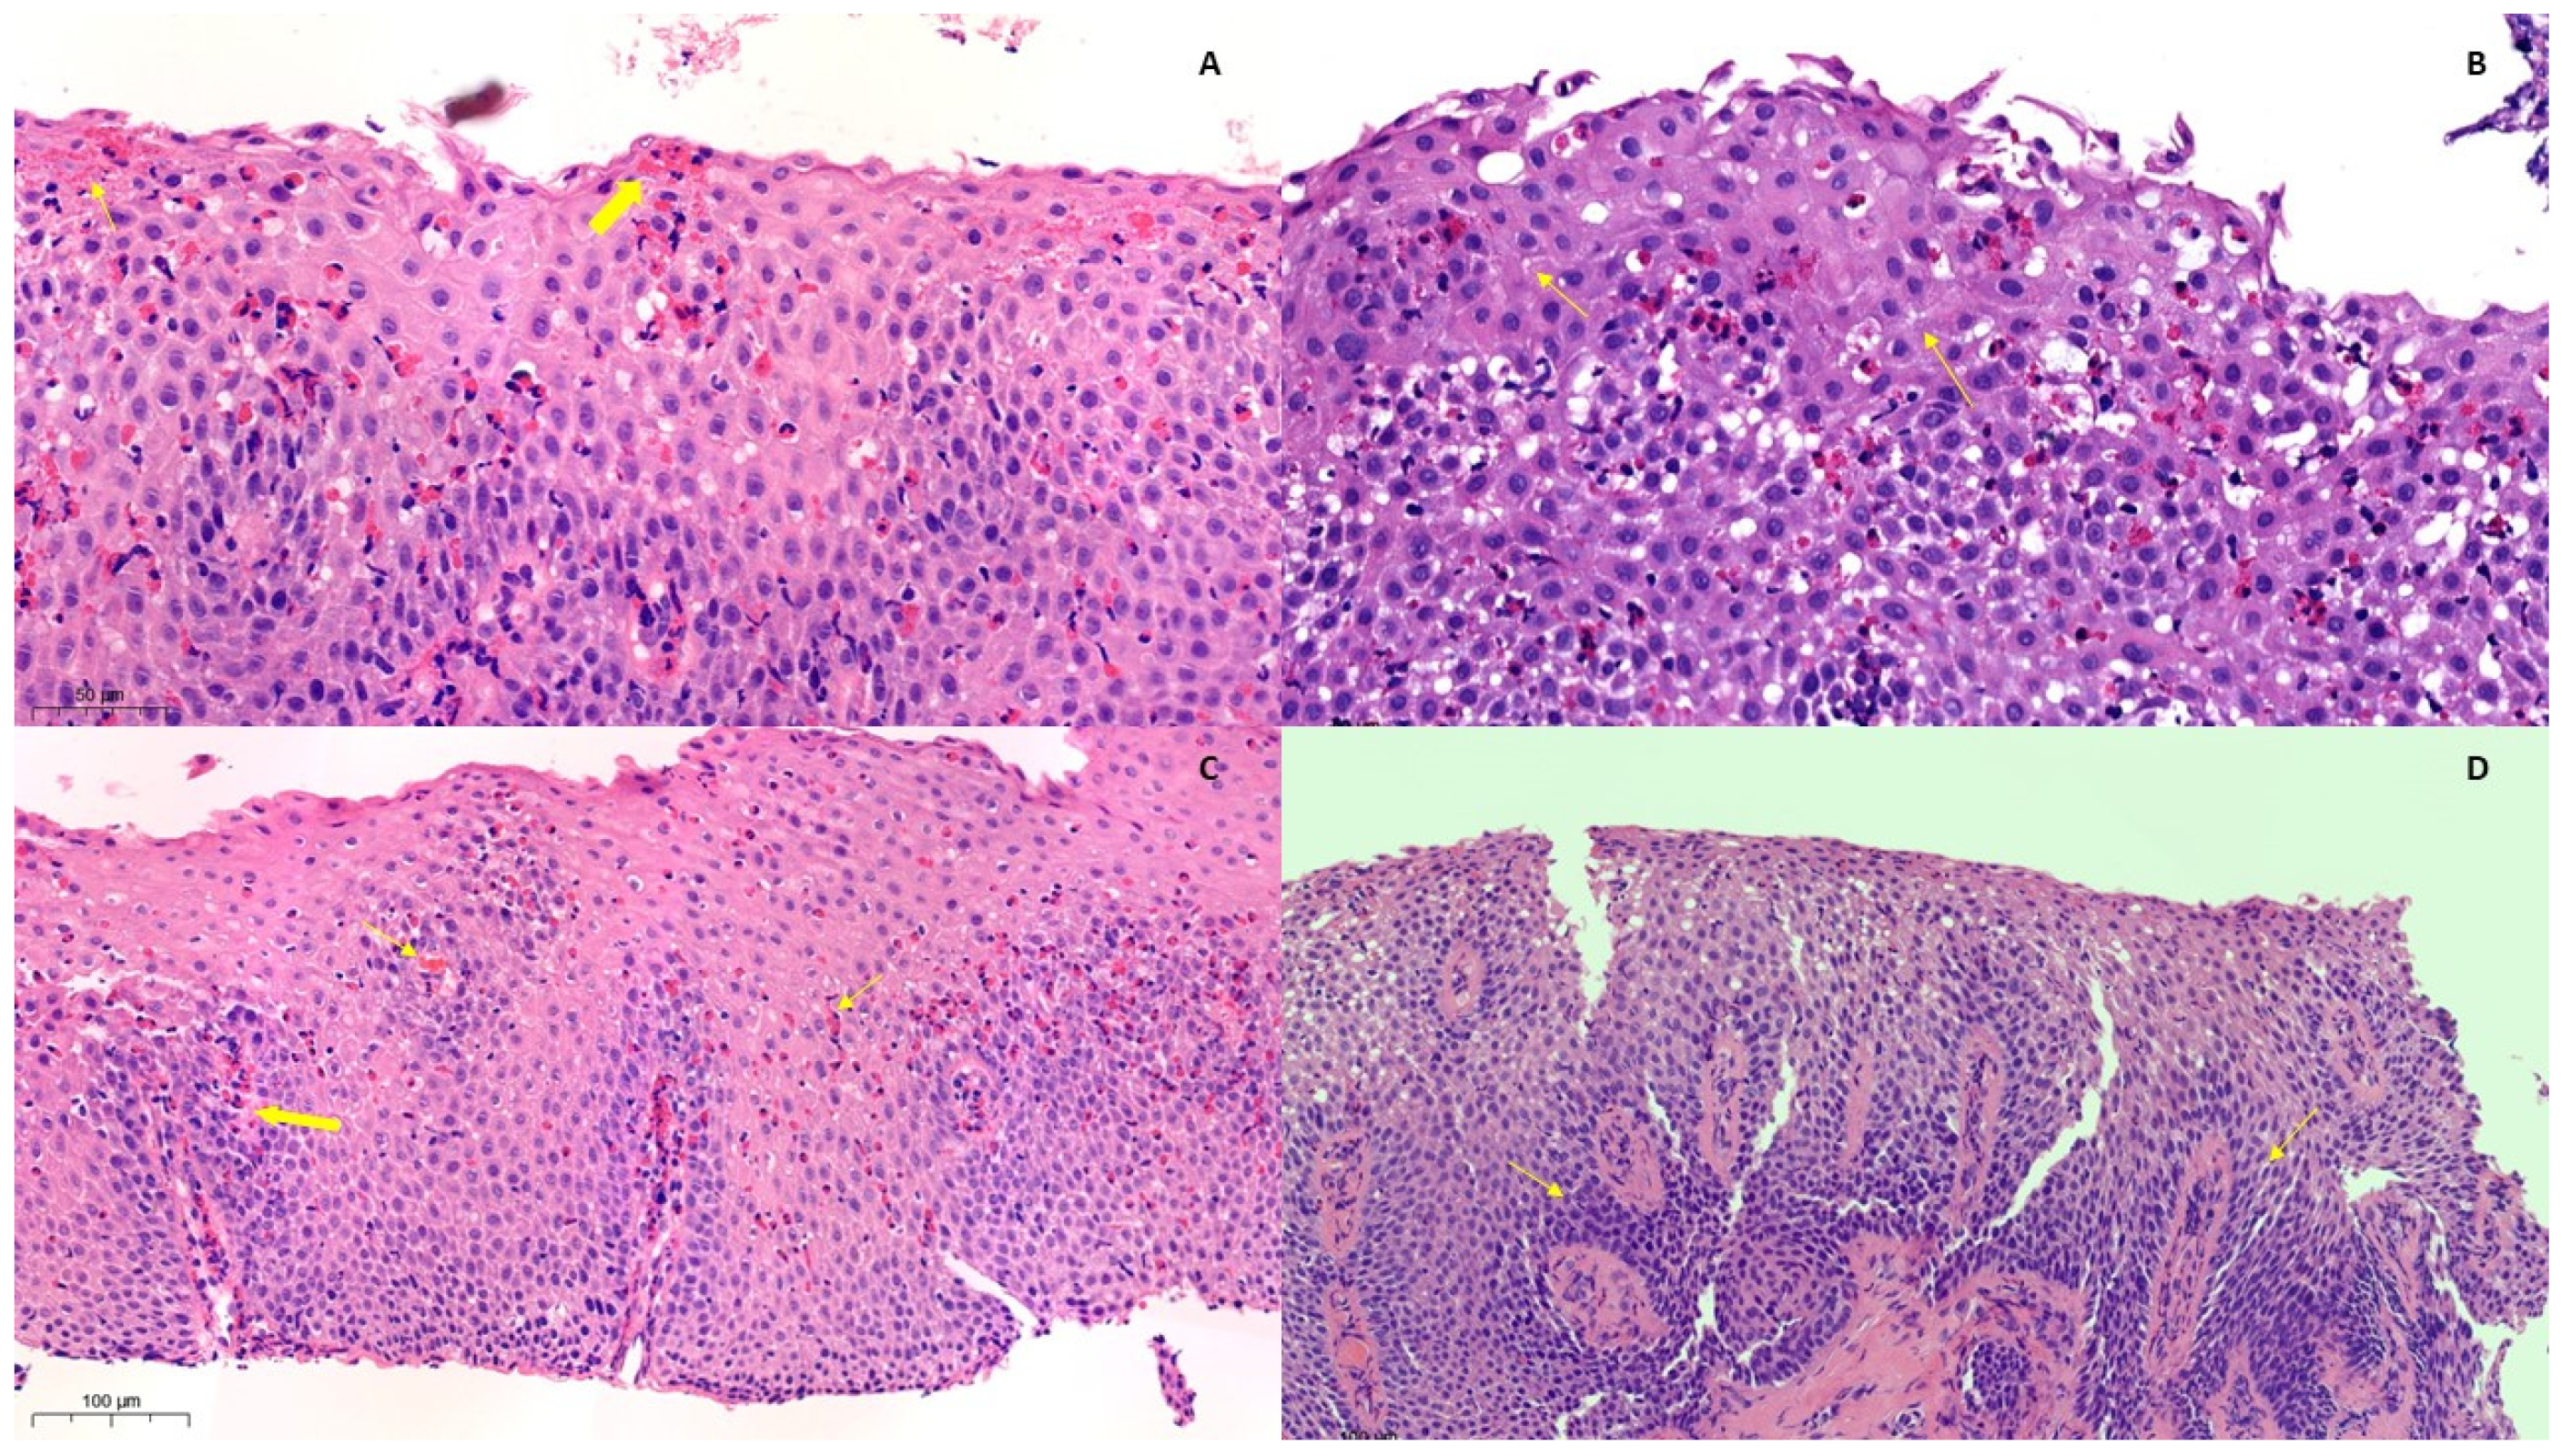

2.3.1. Histological Features

3.3. Histology

4.3. Histology